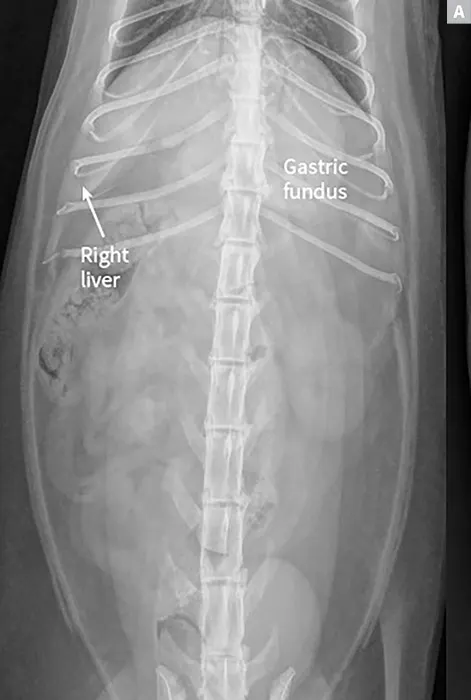

Lateral radiographs of a clinically normal cat (A) and a 14-year-old neutered male domestic shorthair cat (B) presented with icterus and elevated liver enzymes. A normal feline liver should have a sharp, pointed margin (A; arrows) and should not extend past the costal arch; the gastric axis should be parallel to the ribs (A; line). The liver in the icteric cat extends past the costal arch, and has rounded borders (B; arrows). The stomach is displaced caudally (B; line; gastric axis from the fundus to the antrum). An ovoid mineralization (B; arrowheads) is also superimposed with the cranioventral liver in the location of the gallbladder. This cat was diagnosed with cholangitis, lipidosis, and a cholelith.